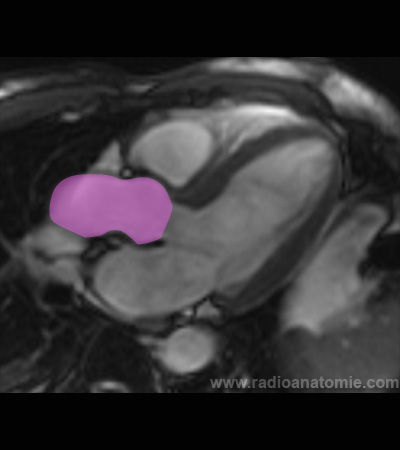

Oreillette gauche